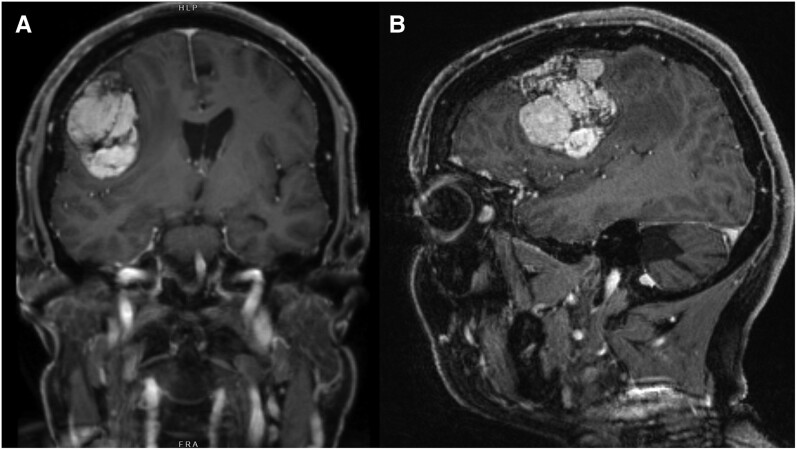

孕激素相关脑膜瘤是醋酸环丙孕酮(CPA)的一种罕见并发症,醋酸环丙孕酮是一种抗雄激素,通常用于变性人和性别多样化者的女性化激素治疗方案。据观察,这种疾病与剂量反应有关,尤其是长期暴露于每天≥50 毫克的剂量时;然而,低于多少剂量使用 CPA 才是安全的,目前仍不清楚。我们在此报告了两名使用 CPA 的变性女性患脑膜瘤的病例。这些病例的新颖之处包括(i) 一名患者出现无症状的巨大脑膜瘤(> 5 厘米),包括需要紧急手术干预的多发性脑膜瘤;(ii) 使用高剂量、长疗程和低剂量、短疗程 CPA 均出现脑膜瘤;(iii) 一名患者出现 PIK3CA 错义变异,这可能在孕激素相关脑膜瘤的发病机制中发挥作用。我们的病例凸显了这种可能未得到充分报道的不良反应在现实世界中的风险,并强调了临床医生警惕神经系统后遗症的重要性。我们建议使用能维持充分雄激素抑制的最低剂量 CPA,并酌情考虑使用其他抗雄激素。

Progestin-associated meningioma is a rare complication of cyproterone acetate (CPA), an anti-androgen commonly prescribed in feminizing hormone therapy regimens for transgender and gender-diverse individuals. A dose-response association has been observed, particularly with longer-term exposure to doses ≥ 50 mg daily; however, the dose below which CPA use is safe remains unclear. We herein report the cases of 2 transgender women using CPA who developed meningioma. Novel aspects of our cases include: (i) the presence of symptomatic giant meningiomas (> 5 cm), including multiple meningiomas in one patient, requiring urgent surgical intervention; (ii) meningioma development with both high-dose, long duration and low-dose, shorter duration CPA; and (iii) the presence of a PIK3CA missense variant in one patient, which may play a role in the pathogenesis of progestin-associated meningioma. Our cases highlight the real-world risk of this likely underreported adverse effect and underscore the importance of clinician vigilance for neurological sequelae. We suggest using the lowest dose of CPA that maintains adequate androgen suppression, with consideration of alternative anti-androgens where appropriate.